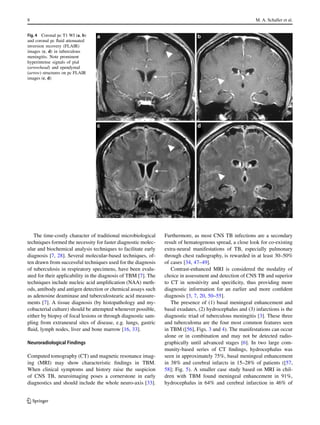

Fig. 4 Coronal pc T1 WI (a, b)

and coronal pc fluid attenuated

inversion recovery (FLAIR)

images (c, d) in tuberculous

meningitis. Note prominent

hyperintense signals of pial

(arrowhead) and ependymal

(arrow) structures on pc FLAIR

images (c, d)

Contrast-enhanced MRI is considered the modality of

choice in assessment and detection of CNS TB and superior

to CT in sensitivity and specificity, thus providing more

diagnostic information for an earlier and more confident

diagnosis [3, 7, 20, 50โ€“55].

The presence of (1) basal meningeal enhancement and

basal exudates, (2) hydrocephalus and (3) infarctions is the

diagnostic triad of tuberculous meningitis [3]. These three

and tuberculoma are the four most common features seen

in TBM ([56], Figs. 3 and 4). The manifestations can occur

alone or in combination and may not be detected radio-

sures and the tentorium [3]. In MRI, Parmar et al. sug-

gest that pc fluid attenuated inversion recovery (FLAIR) se-

quences provide a higher specificity compared to pc T1 WI

in detection of leptomeningeal enhancement, while show-

ing a similar sensitivity ([62]; Fig. 4). Additional DWI may